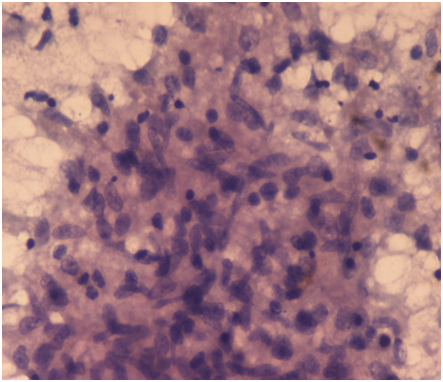

A 50year old female presented to the plastic surgery clinics with complaints of irregular, 2x1.5cm, solid to cystic swelling with excoriation at the upper lip, situated between the midline and angle of the mouth since 2months (Figure 1). There was no history of fever, cough, loss of appetite, weight loss, anti-tubercular treatment intake or contact and any lymphadenopathy. Fine needle aspiration biopsy showed typical epithelioid cell clusters with foci of caseous necrosis (Figure 2). Excision biopsy of the lesion was performed and sent for the histopathological examination. Grossly multiple small irregular brownish white soft to firm tissue pieces, 1.8cm in aggregate was received. Microscopically dense lymphocytic infiltrate in the underlying dermis with fibrosis and well defined epithelioid granulomas with langhan’s giant cells and widespread foci of caseous necrosis was seen (Figure 3). AFB stains revealed magenta colored acid fast tubercular bacilli. A histopathological diagnosis consistent with tuberculosis of lip was given. A nine-month anti-TB drug regimen of isoniazid, rifampicin, pyrazinamide, and ethambutol, was prescribed and within four weeks after initiation of the anti-TB treatment, the labial lesion strikingly improved.

Figure 2 Fine needle aspiration biopsy showed typical epithelioid cell clusters with foci of caseous necrosis. Papx40X.